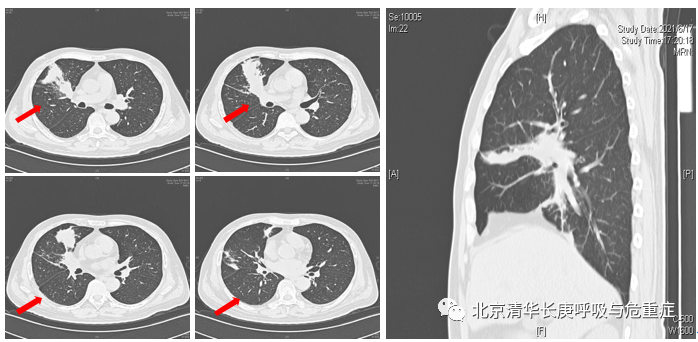

一位来自于山东的52岁男性患者,因发热、肺部感染,病情持续进展,外院无法确诊,而来我院就诊。患者入院前1个多月开始出现反复发热,体温波动在37.8℃-38.2℃,伴有畏寒、乏力,纳差。外院支气管肺泡灌洗液培养及二代测序等未发现明确致病菌。外院考虑真菌感染可能,静脉应用两性霉素B、卡泊芬净及亚胺培南西司他汀等药物效果不佳。为求进一步诊治而来我院。既往诊断为急性髓系白血病6个月,曾行化疗4次及脐带血造血干细胞移植治疗。吸烟史30年余,约20支/日,偶有饮酒,近期结核患者接触史。入院后查外周血白细胞减少,CRP和血沉增高,痰涂片及痰培养阴性,呼吸道病原九项阴性,G试验和GM试验均阴性。T-SPOT-TB阴性。入院胸部CT可见右肺中叶、下叶多发斑片和片状渗出实变影(图2)。

图2入院胸部CT可见右肺中叶和右肺下叶内基底段可见多发斑片和片状肺内渗出实变影(箭头所示)。